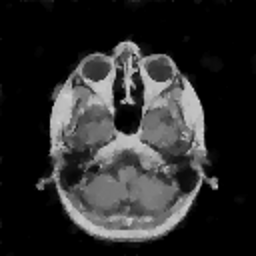

VII-C Experiments with real-life data

Reconstruction of real-life MRI images has been the next step in our comparative study. To this end, the data set of [19] have been used herein. The data were obtained at the University Hospital of Ghent and it is publicly available at http://telin.ugent.be/~sanja/Sanja_files/Software/MRIprogram.zip. The data contains a sagittal and an axial scan of a human brain, which are shown in Fig. 10 and Fig. 11, respectively.

The reconstruction results obtained for each of the tested images using the proposed and reference methods are shown in Subplots (b)-(f) of Fig. 10 and Fig. 11, respectively. From these figures, it can be seen that the proposed algorithms result in higher-contrast reconstructions of better visual clarity as compared to the reference approaches. The difference is particularly evident for the case of Fig. 11, where the proposed algorithms result in less noisy images, while exhibiting higher effective resolution and contrast.

Refer to caption

Figure 11: (a) Axial MRI scan; (b)-(f) Reconstruction results obtained using TVDN, WDN, GNLM, NLMS and NLMR, respectively.